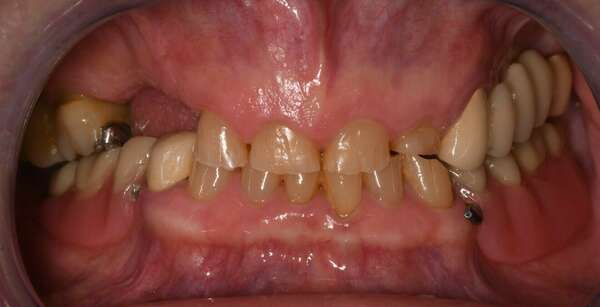

Patiente de 65 ans, sans problème de santé, venue consulter pour une réhabilitation complète.